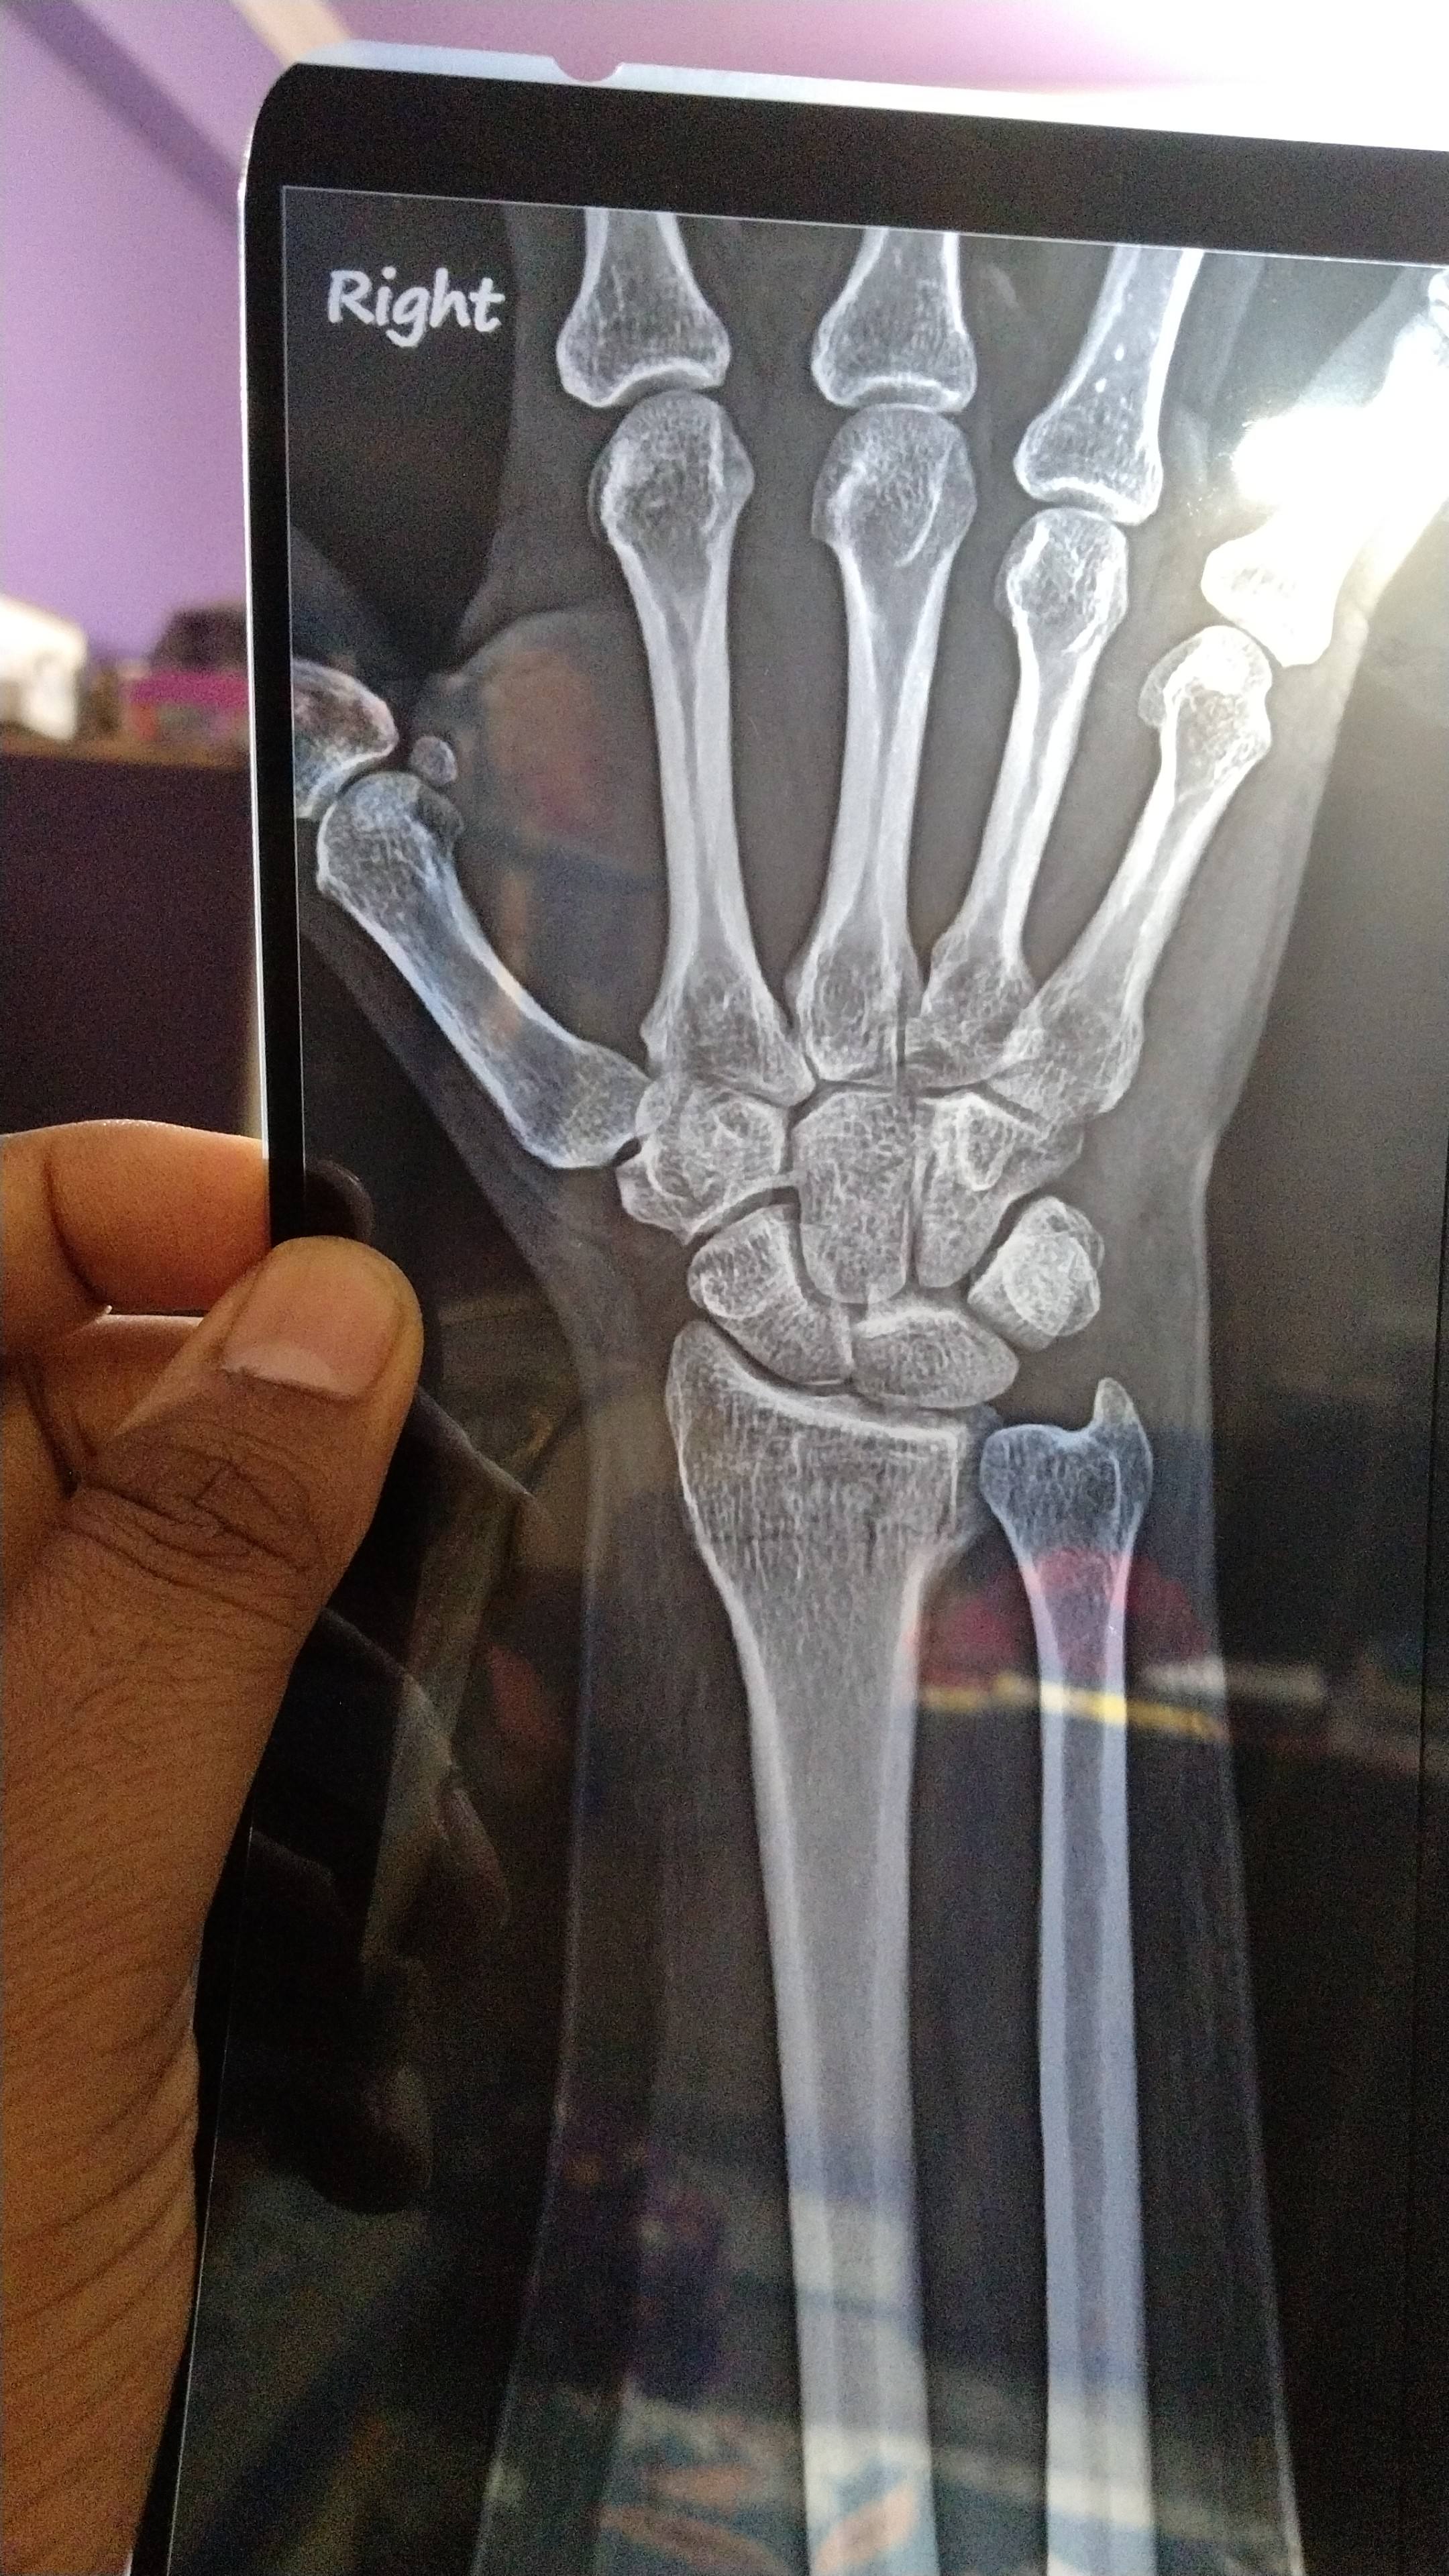

Thia is not proper joined it . Pain is very much how to solve it